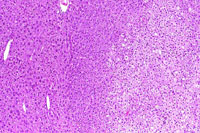

This adenoma has a partial rim of basophilic cells while the remaining cells are pale.

This mixed hepatocellular adenoma is comprised of an admixture of basophilic and pale staining hepatocytes.